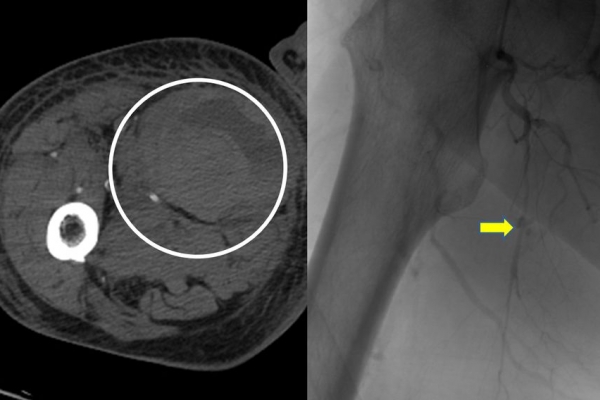

Συνοπτικά υπό την καθοδήγηση του αγγειογράφου, αναγνωρίζεταιτο παθολογικό αγγείο-αγγεία και με ειδικούς καθετήρες και μικροκαθετήρες, διοχετεύονται εμβολικά υλικάόπως μικροσφαιρίδια ή coils, ώστε να αποφραχθεί ή να μειωθεί η παθολογική αγγείωση.